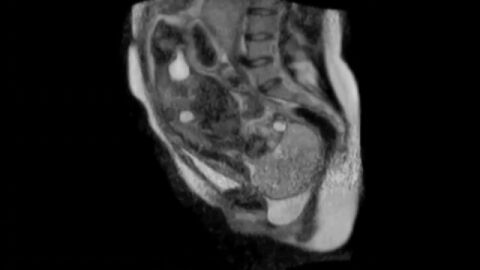

UNA MUJER DA A LUZ EN UNA MÁQUINA DE RESONANCIA MAGNÉTICA

Es la primera vez que podemos ver un parto desde dentro. La grabación la ha distribuído el 'American Journal of Obstetrics and Gynecology'. Es un caso de una mujer que, en Alemania, dió a luz en un aparato de resonancia magnética y el parto quedó grabado.

La experiencia se remonta al año 2010. Una mujer de 24 años dio a luz en un aparato de resonancia magnética en Alemania y todo quedó grabado.

En las imágenes puede verse el momento en el que el niño está a punto de salir del útero materno. Se ven los movimientos de la madre y el niño, y el instante en el que el bebé saca la cabeza.

El pequeño pesó dos kilos y 585 gramos. Todo se desarrolló de manera normal y tanto la madre como el niño fueron dados de alta a los dos días.